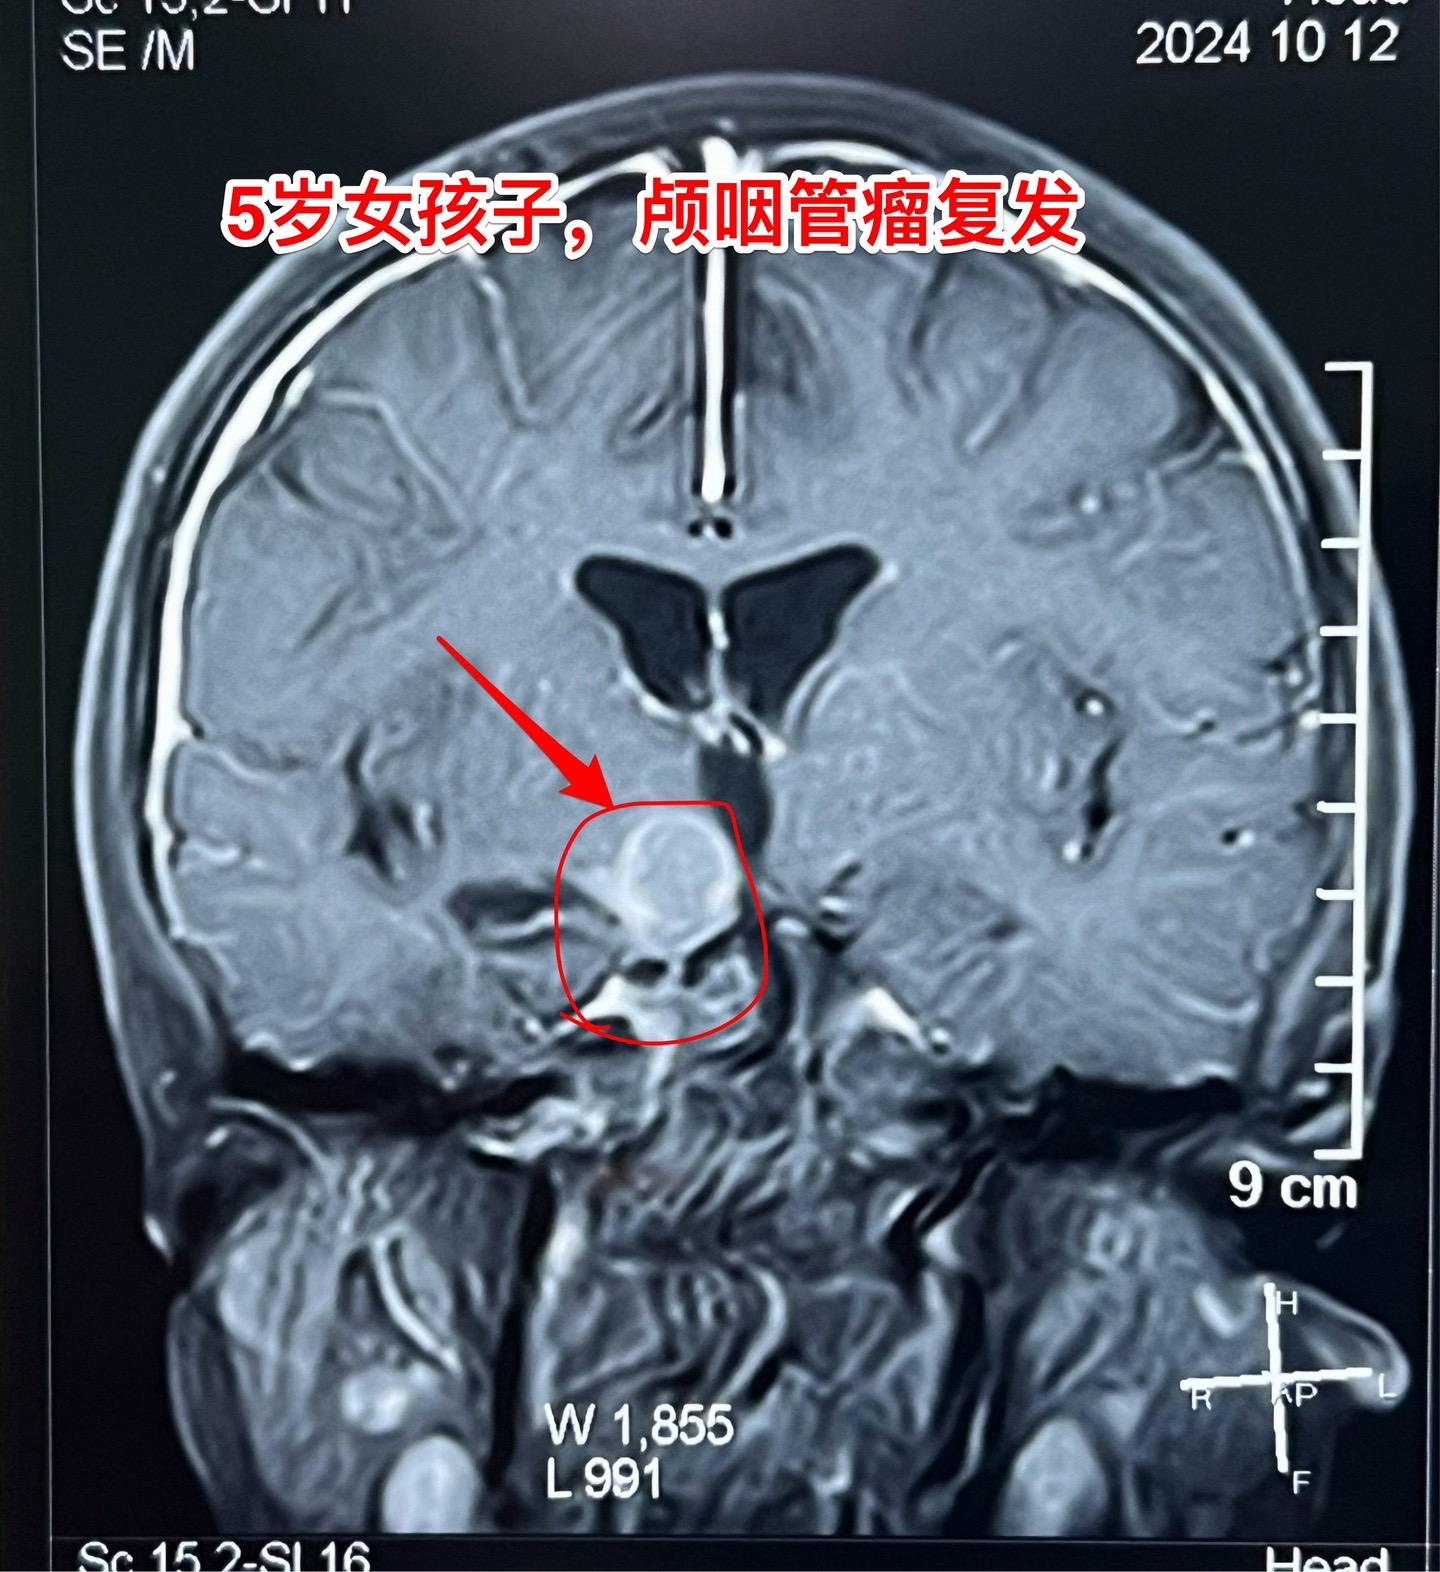

复发颅咽管瘤的手术难度好判断吗?5岁广州的女孩子,颅咽管瘤复发了。第一次手术在广州市某医院作的。现有的CT和磁共振显示肿瘤是一个囊,体积也不大。 这样的复发颅咽管瘤手术难度大吗? 一眼看上去,这个颅咽管瘤切除的难度似乎不大。但是在手术过程中发现,肿瘤与周围组织粘连紧密,分离过程很是艰难。 另外还有一个更难的难题,那就是这个肿瘤周围及其它位置有很多个散在的细小钙化斑。术中所见的钙化及肿瘤虽然切除了,术野之外的地方是不是还潜藏着钙化呢? 所以,复发